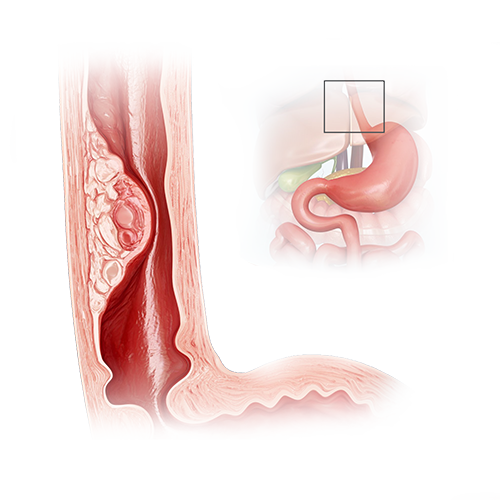

Рак Желудка Симптомы Фото

Рак Желудка Симптомы Фото 111 фото